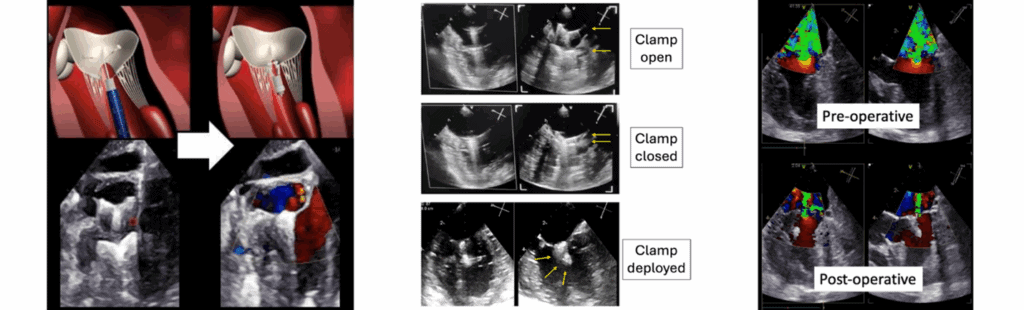

The TEER procedure is performed on a beating heart and uses a specially designed “V-Clamp” to bring the mitral valve leaflets together, reducing the severity of mitral regurgitation. The procedure is guided by real-time 3D echocardiography, allowing precise placement and immediate assessment of effectiveness.

TEER is performed via a small thoracotomy (6–8 cm incision). After surgery, patients typically have a routine recovery, with a chest drain for 6-12 hours, and minimal need for ICU care. Almost all dogs are discharged by 2-days post-procedure.